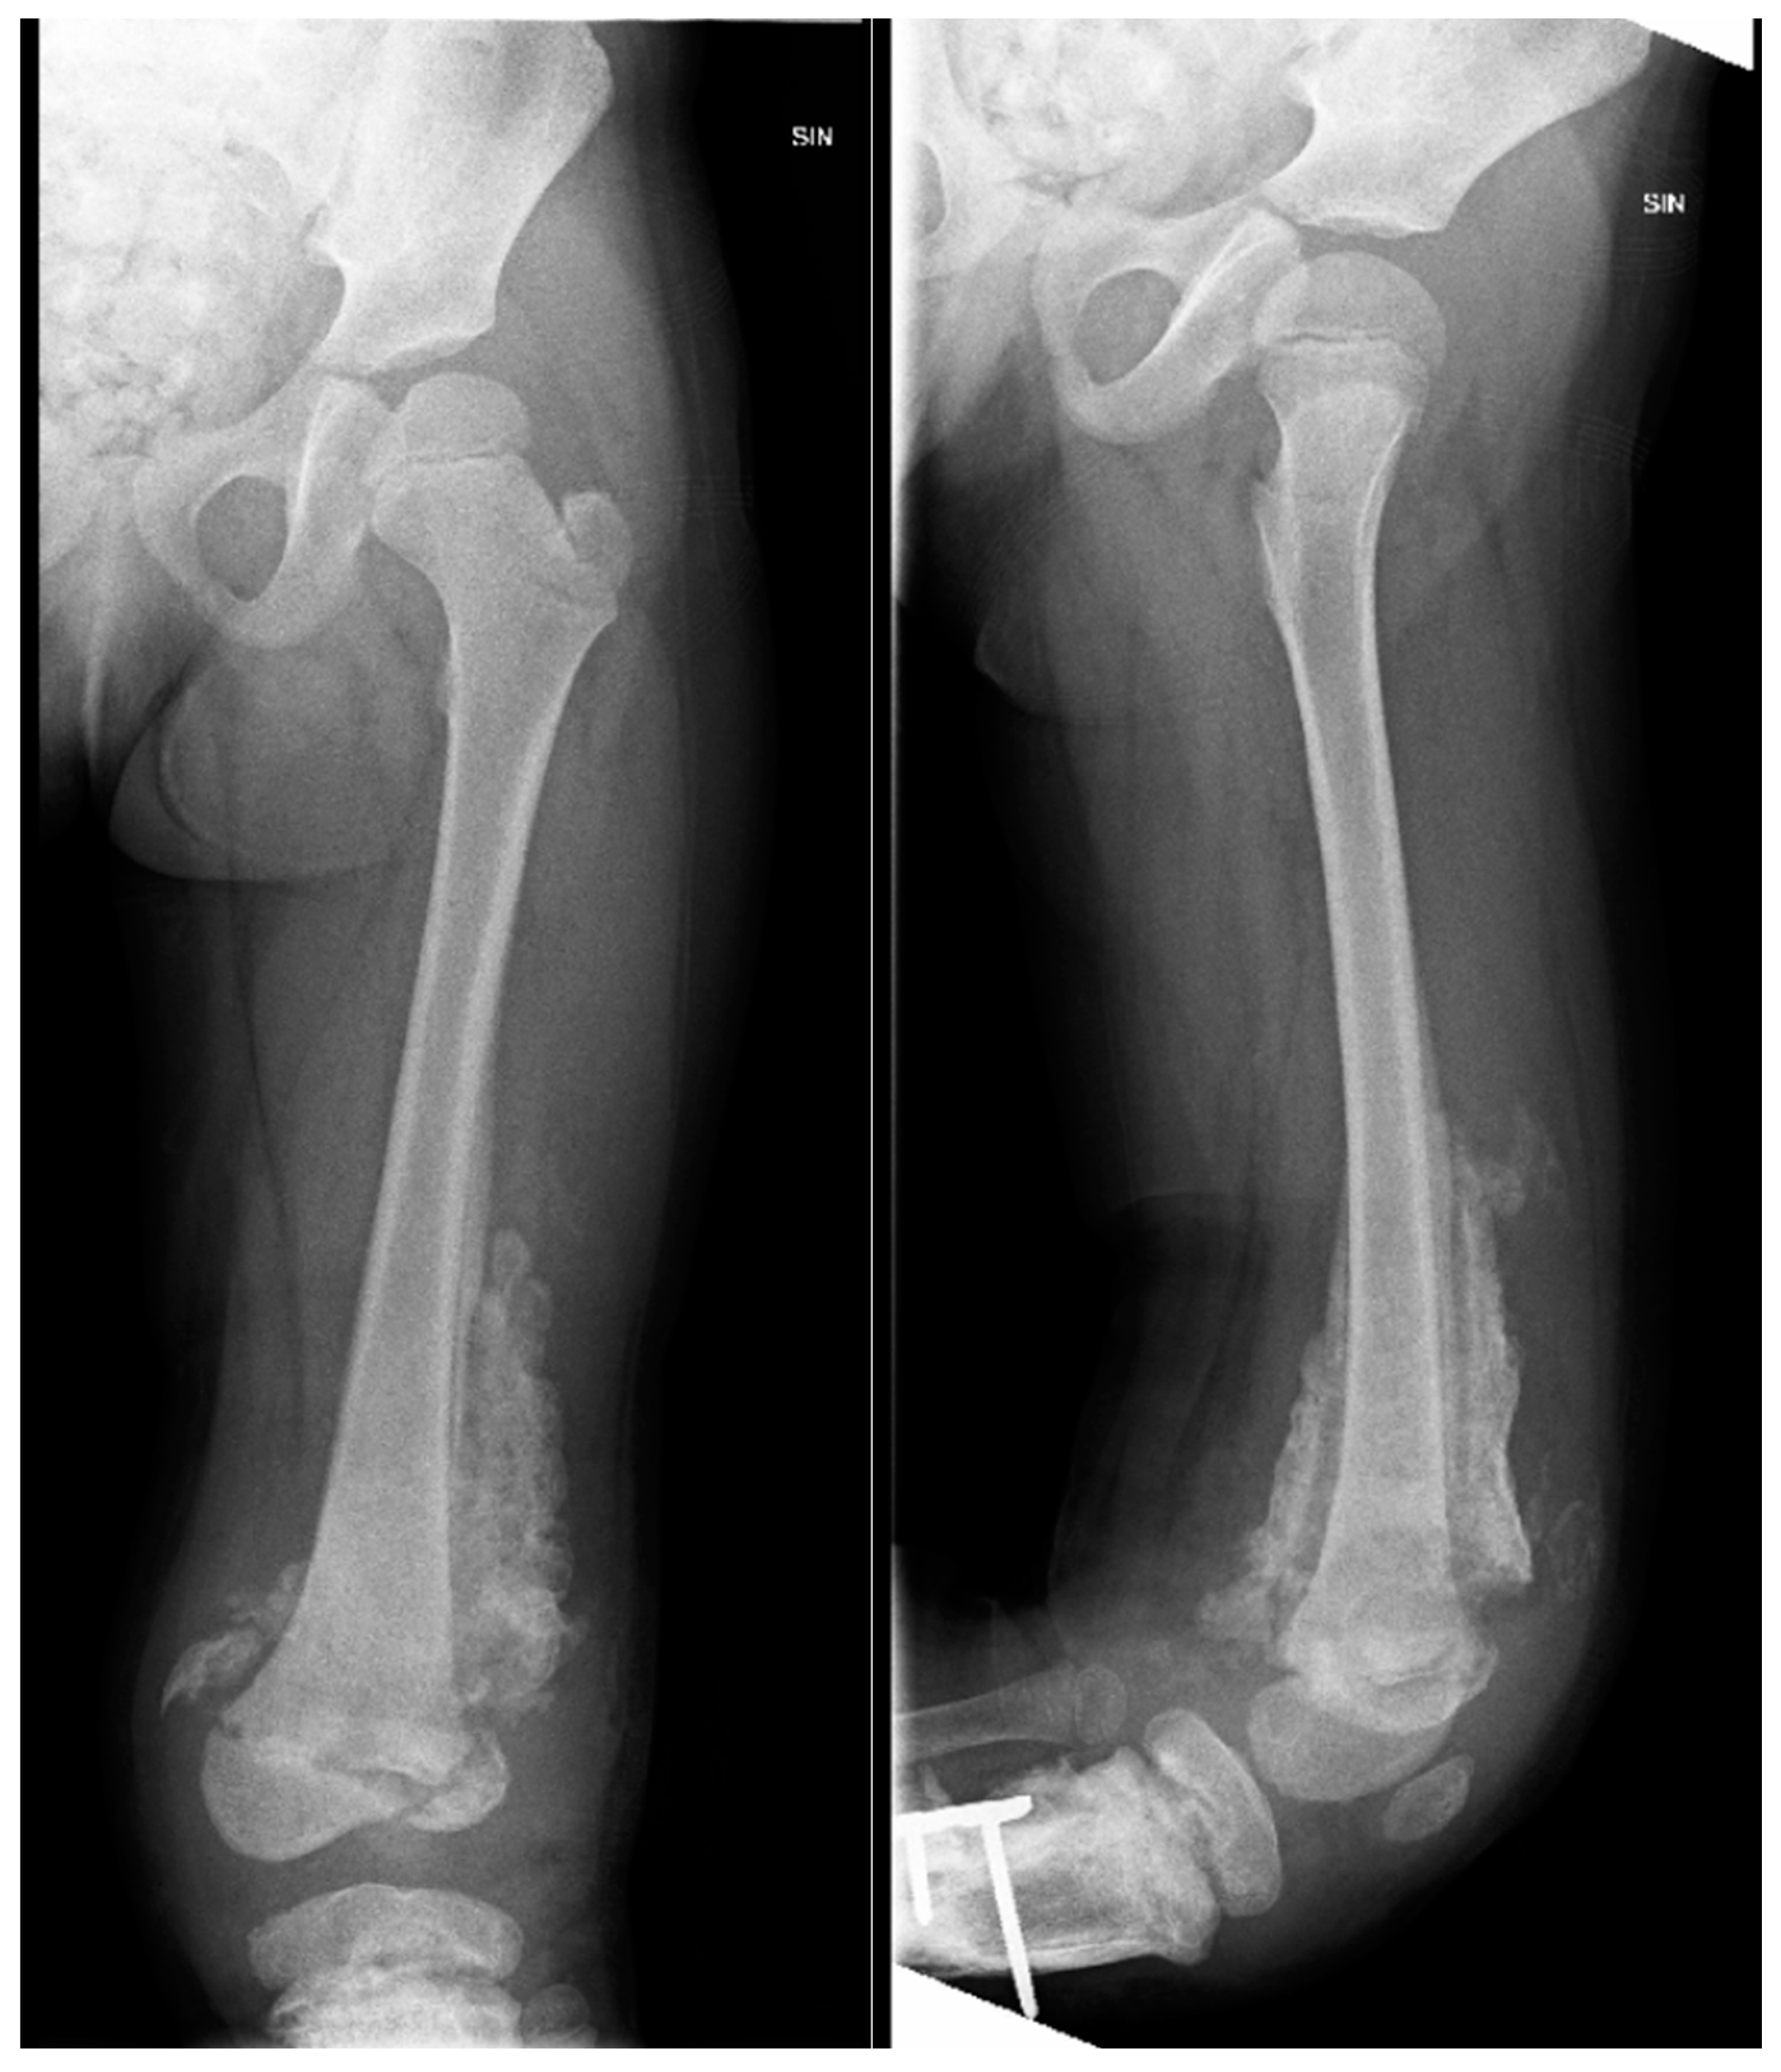

Figure 6. X-ray examination of left lower leg in AP and lateral projections shows posttraumatic chronic osteomyelitis of left tibial diaphysis. After fixation with a locking plate and implantation of resected fibula diaphysis fragment, consolidation forms near implanted bone, with slightly increased soft tissue calcifications and sclerosis.

Figure 8. The X-ray examination of the distal third of the thigh to the lower leg in AP and lateral projections reveals an inflammatory process in the distal femur and proximal tibial growth zone, wide areas of destruction, and massive ossification around the tibia diaphysis.

Figure 9. CT imaging shows an inflammatory process in the distal femur and proximal tibial growth zone, with wide areas of destruction, including the left knee joint bones, and massive ossification around the tibia diaphysis, without signs of convalescence.